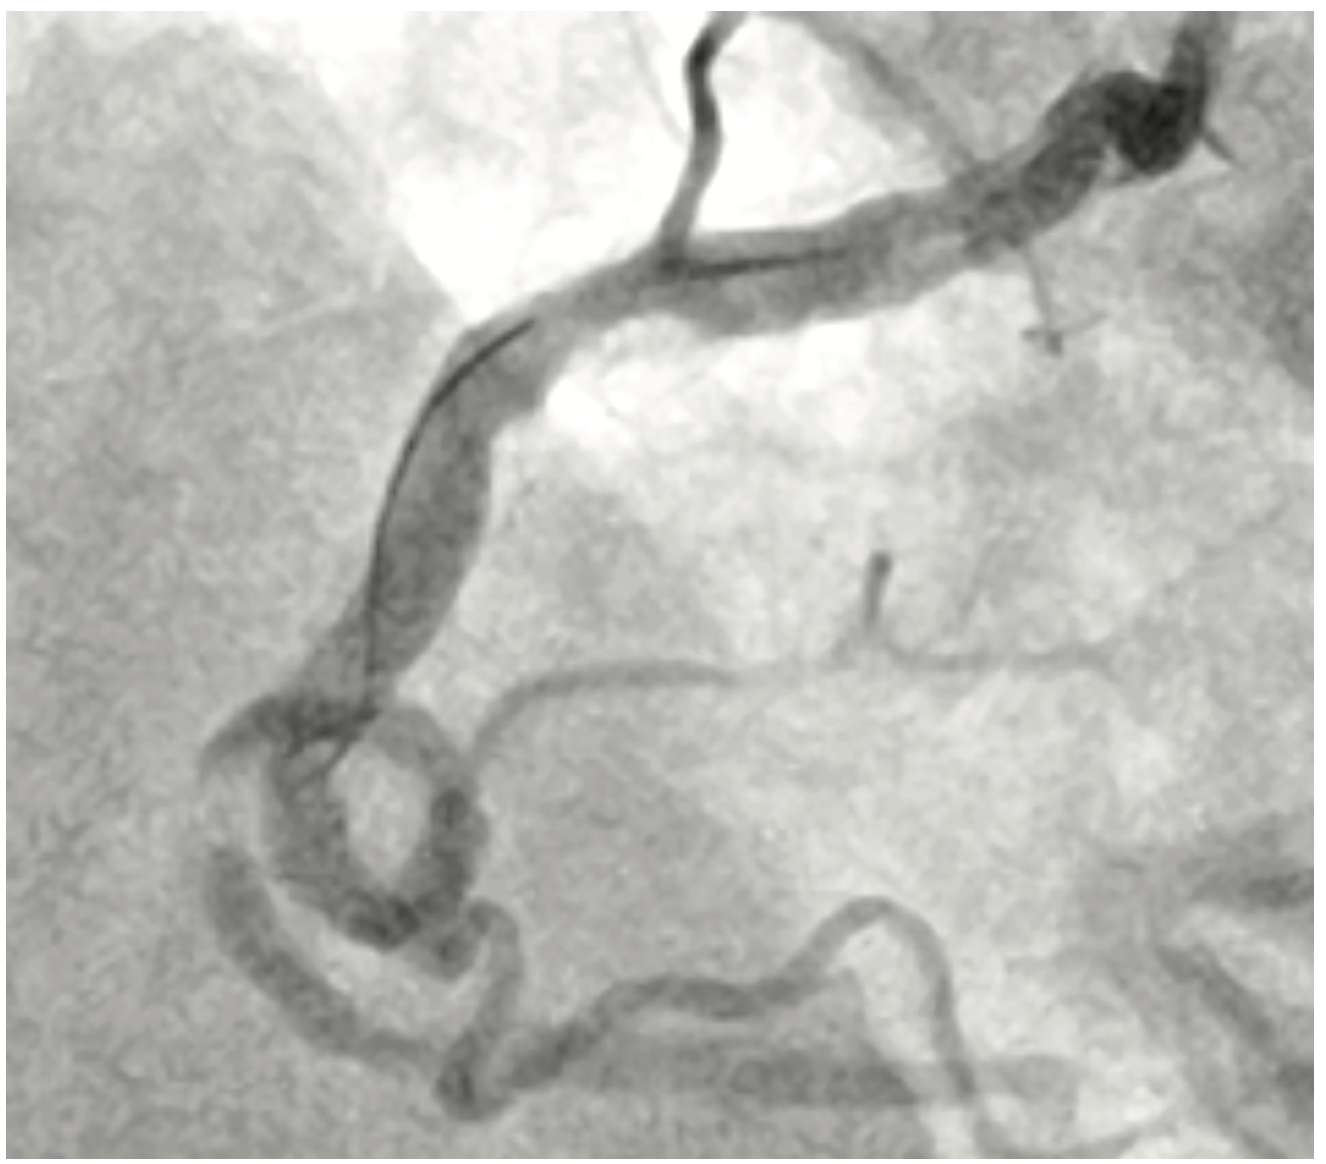

The RCA was engaged with the AL1 7 French (Fr) guide catheter via the right radial approach. After administering heparin to a goal ACT of >250s, we advanced a floppy coronary wire to the distal PDA using a microcatheter and subsequently exchanged it for a supportive guidewire. The loop did not unravel after placing the support wire and hence we introduced a 7 Fr guide catheter extension. We serially pre-dilated the lesions initially with a 1.5 mm x 15 mm, 2.0 mm x 20 mm TAKERU balloon catheter at 14 atm (Figure 3). We advanced the guide catheter extension further to the mid RCA using balloon catheter-assisted tracking and delivered several overlapping drug-eluting stents which were aggressively post-dilated with noncompliant balloons. Final angiography (Figure 4) showed no evidence of dissection or perforation. There was TIMI-3 flow and 0% residual stenosis. The patient was placed on triple therapy (aspirin 81 mg daily/clopidogrel 75 mg daily/apixaban 5 mg BID) for one month along with a proton pump inhibitor later dual therapy for 12 months.